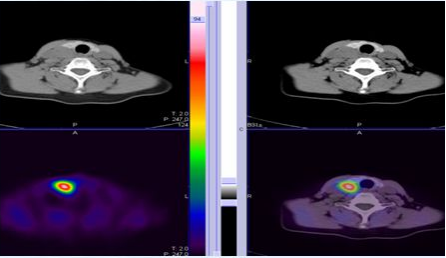

1.原发性甲状旁腺功能亢进显像:

原发性甲状旁腺功能亢进时,多为单发的甲状旁腺腺瘤引起(图3)。甲状旁腺显像对甲状旁腺功能亢进患者术定位有高敏感性和特异性。

图3 甲状旁腺腺瘤